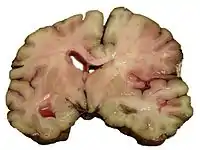

![]() КТ-сканування головного мозку демонструє ішемічний інсульт у правій півкулі (на зображенні ліворуч). КТ-сканування головного мозку демонструє ішемічний інсульт у правій півкулі (на зображенні ліворуч). | |

Комп'ютерна томографія (КТ) і магнітно-резонансна томографія (МРТ) — найважливіші діагностичні дослідження при інсульті. КТ у більшості випадків дозволяє чітко віддиференціювати «свіжий» крововилив у мозок від інших типів інсультів, МРТ найкраща для виявлення ділянок ішемії, оцінки поширеності ішемічного ушкодження і пенумбри (це особливо важливо в перші 12-24 години захворювання, коли методом КТ ішемічний інсульт може не візуалізуватися). Також за допомогою цих досліджень можна виявляти первинні і метастатичні пухлини, абсцеси мозку і субдуральні гематоми. Якщо спостерігається ригідність потиличних м'язів, але відсутній набряк диска зорового нерва, люмбальна пункція в більшості випадків дозволить швидко встановити діагноз крововиливу в мозок, хоча при цьому зберігається незначний ризик виникнення синдрому «вклинення» мозку. У випадках, коли є підозри на емболію, люмбальна пункція необхідна, якщо передбачається застосування антикоагулянтів. Люмбальна пункція має також важливе значення для діагностики розсіяного склерозу і, крім того, може мати діагностичне значення при нейроваскулярному сифілісі та абсцесі мозку[20].